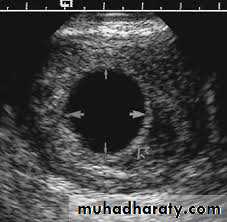

Medical applicationClinical assessment ovulation